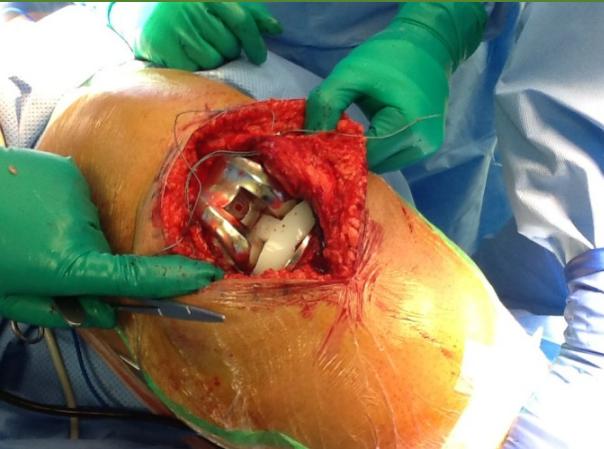

| K-wire (Kirschner Wire) | Indications: Pediatric fractures, small bone fractures in adults. Advantages: Easy to apply/remove. Disadvantages: Not stable alone, risk of infection. | , , , , , ![]() |